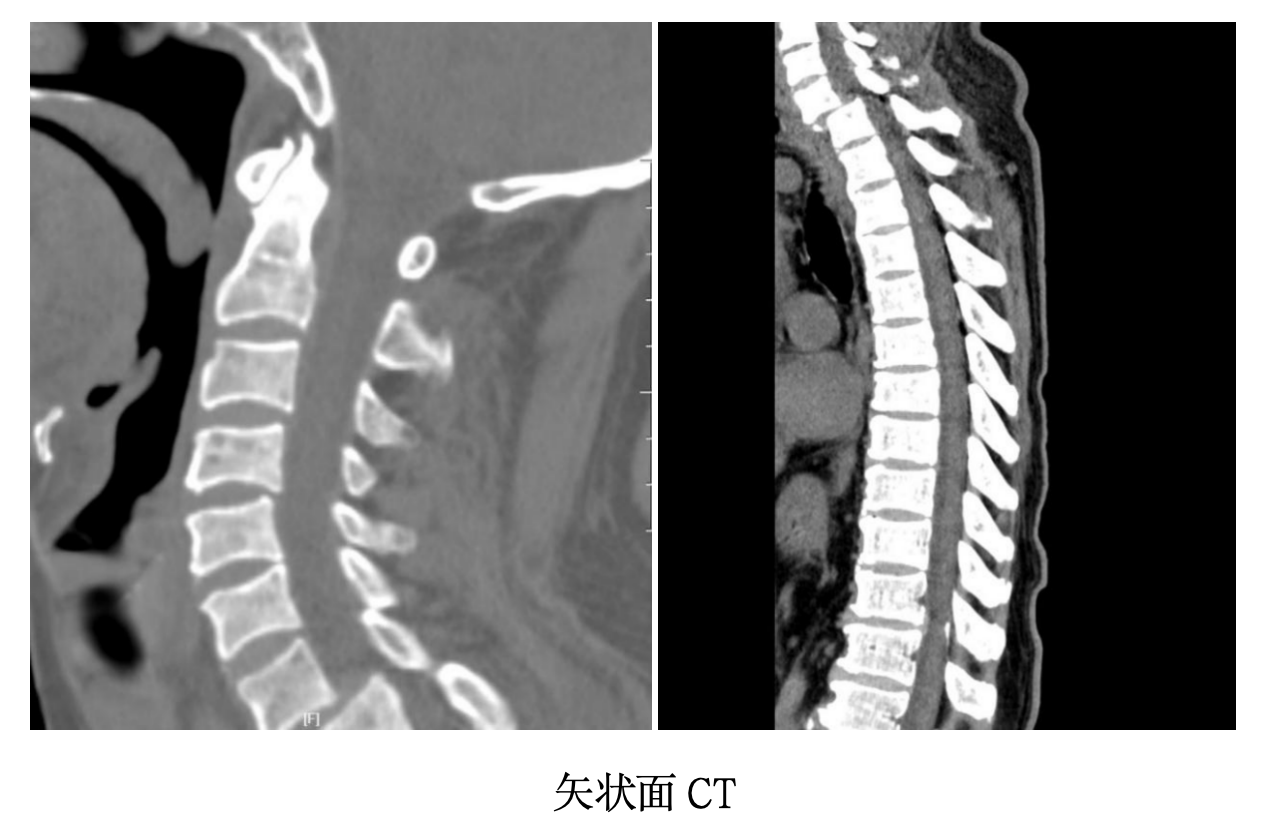

不久前,一位因从3米高处坠落导致背部受伤的患者,因颈胸交界处剧烈疼痛来到该院。经CT检查,结果显示:颈7椎体与胸1椎体之间发生了严重脱位,并伴有双侧关节突交锁。

然而,术中牵引复位效果不佳,前路暴露至椎前筋膜时仍可触及明显“阶梯感”,且由于胸骨、锁骨和肩胛骨的遮挡,术中C臂机无法清晰显示脱位情况,继续操作风险极高。

2.复位固定困难:胸廓入口有骨质遮挡,传统C臂机透视观察困难,置钉角度刁钻。